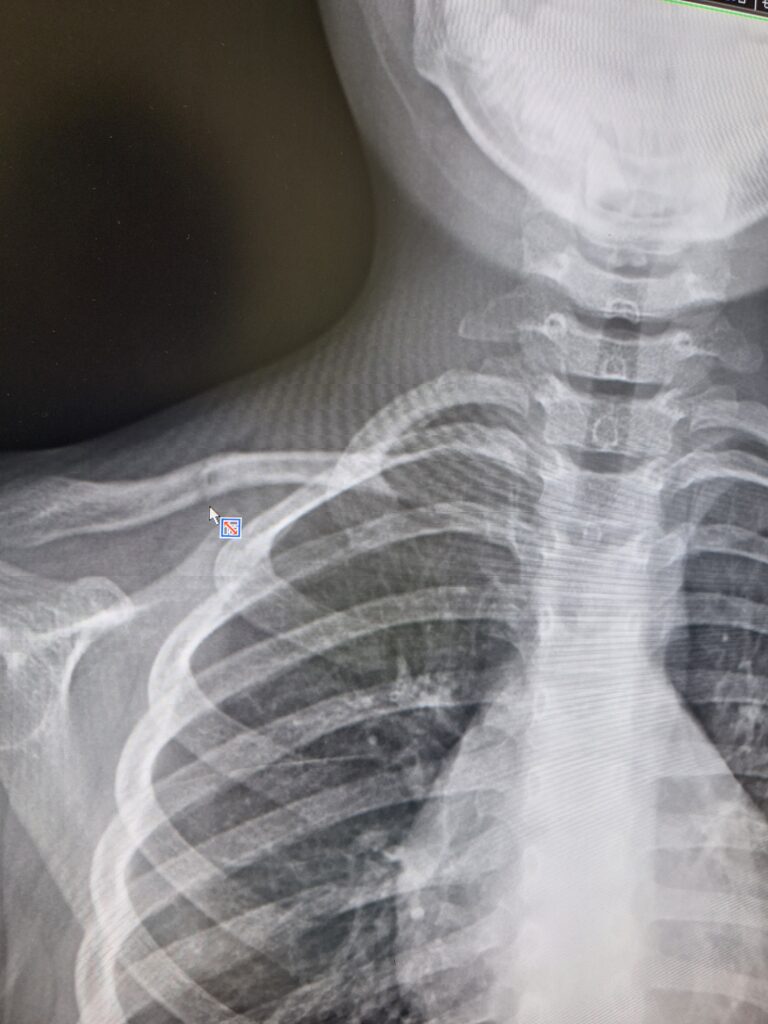

でも先生が腕の上がりが左右違うから レントゲンを撮ってみようと撮影してくれたところ

「はい 鎖骨折れてるね」って おぉぉぉぉそっちだったのね(笑)

鎖骨固定ベルトをしてもらい しばらく幼稚園もお休みすることにしました☆